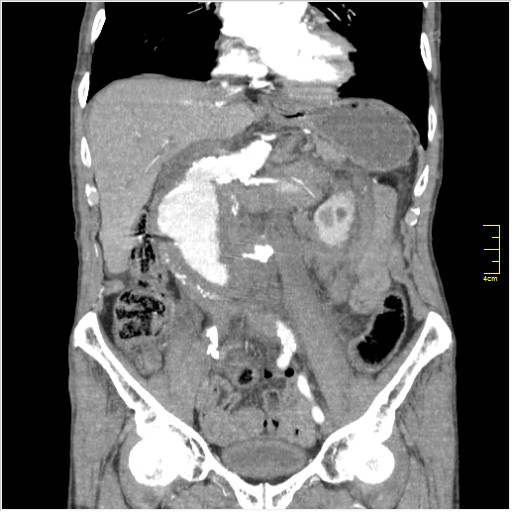

Пациент Т. 64 года, обратился на КТ брюшной полости амбулаторно (!), по направлению семейного врача с диагнозом abdominal mass, буквально: образование брюшной полости.

Huge abdominal aorta aneurism. Simple renal cortical cysts (Bosniak type 1).